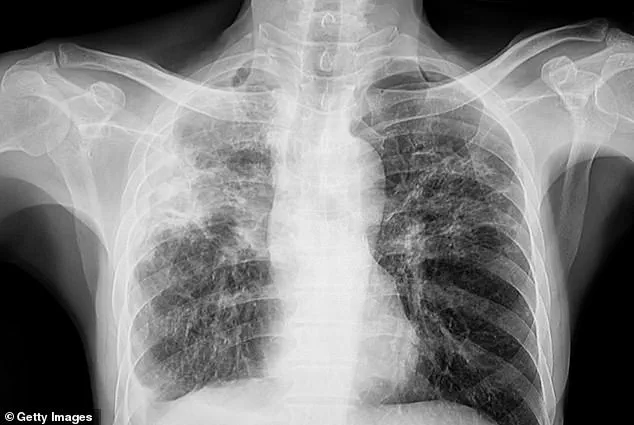

The three patients, all diagnosed with active tuberculosis—a condition where the bacteria is multiplying in the lungs—have no known connection to one another, suggesting separate sources of infection.

In the early stages of the disease, symptoms may include a persistent, unexplained cough, sometimes accompanied by coughing up blood or chest pain.

As the disease progresses, patients may experience unexplained weight loss, loss of appetite, fever, and night sweats.

In later stages, severe breathing difficulties and extensive lung damage can occur, with the infection potentially spreading to other organs such as the liver or spine, causing pain in these areas.

The consequences of untreated tuberculosis can be dire.

Patients often succumb to respiratory failure or complications from lung damage that prevent the body from absorbing enough oxygen.